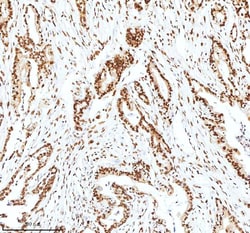

Reconstitute with 0.2 mL of distilled water to yield a concentration of 500 μg/mL. Positive Control - WB: human LNCAP whole cell, human Hela whole cell, human 293T whole cell, human HepG2 whole cell, human Jurkat whole cell, human K562 whole cell, human A549 whole cell, human A431 whole cell. IHC: human bladder cancer tissue, human bladder cancer tissue, human colon adenocarcinoma tissue, human colon adenocarcinoma tissue, human glioblastoma tissue, human glioblastoma tissue, human liver cancer tissue, human liver cancer tissue, human lung adenocarcinoma tissue, human lung adenocarcinoma tissue, human pancreas ductal adenocarcinoma tissue, human pancreas ductal adenocarcinoma tissue, human testicular seminoma tissue, human testicular seminoma tissue. ICC/IF: U2OS cell. Flow: A431 cell. Store at -20°C for one year from date of receipt. After reconstitution, at 4°C for one month. It can also be aliquotted and stored frozen at -20°C for six months. Avoid repeated freeze-thaw cycles.

| Flow Cytometry, Immunohistochemistry (Paraffin), Western Blot, Immunocytochemistry | |